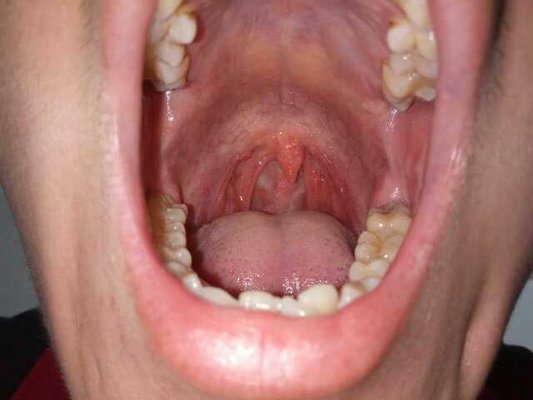

Pharyngitis is a nonspecific inflammation of the pharynx, which is a general term for inflammation caused by various microorganisms. It can exist alone, coexist with rhinitis, tonsillitis and laryngitis, or be a precursor of some diseases. What are the causes and symptoms of pharyngitis? Let's talk about it

Mainly virus and bacteria infection. Most of them are infected by droplets or direct contact. The pharynx of the human body is the passage behind the nasal cavity and oral cavity, which can be divided into three parts: nasopharynx, oropharynx and laryngopharynx. Pharynx is rich in lymphoid tissue, they gather into a mass called tonsil.